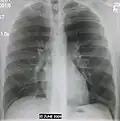

AP CXR showing left lower lobe pneumonia associated with a small left sided pleural effusion -

AP CXR showing right lower lobe pneumonia -

AP CXR showing pneumonia of the lingula of the left lung -

Right upper lobe pneumonia as marked by the circle. -

Left upper lobe pneumonia with a small pleural effusion.

-

Right lower lobe pneumonia as seen on a lateral CXR